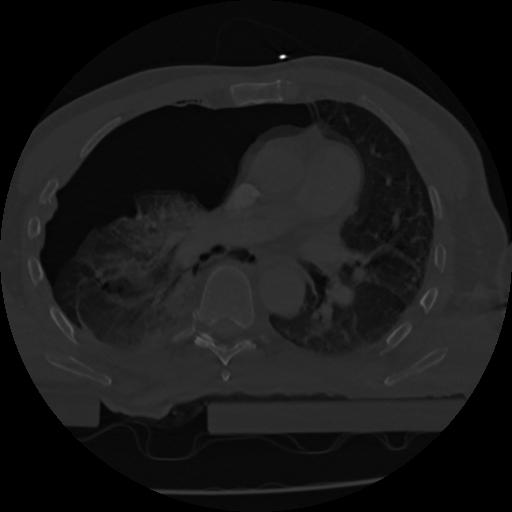

22 ANGIO,CE,Vol,0.5,ANGIO,,